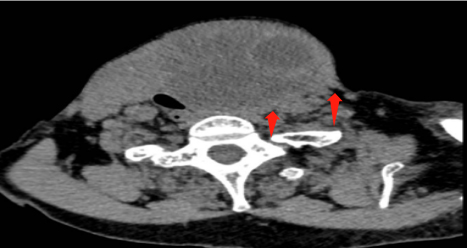

78岁的刘奶奶因颈部巨大甲状腺肿困扰多年,家人带她求医问药,但因种种原因没有继续治疗,今年以来她自感肿块越来越大,严重影响到生活起居,于是家人便带她至我院甲状腺科诊治,在术前的颈部CT显示,肿块已经导致气管、食管明显受压、移位。当务之急是要尽早手术切除,解除压迫。